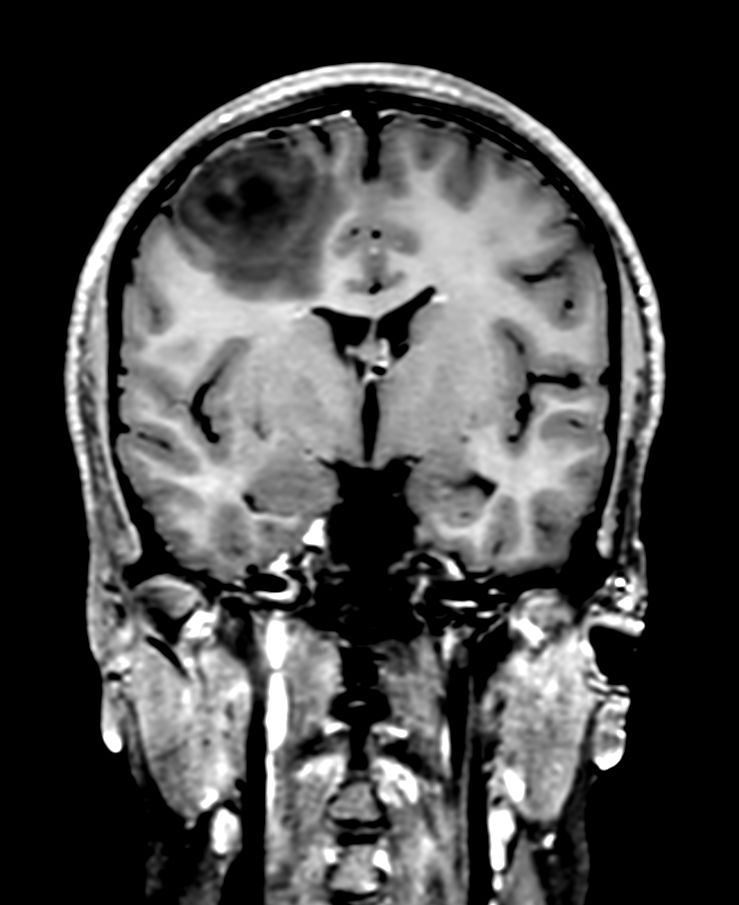

Patient with a brain lesion. ExamCard includes MultiVane XD for motion-free imaging in short scan time, Compressed SENSE to shorten exam time, SWIp to enhance contrast for deoxygenated (venous) blood or calcium deposits, a high resolution 3D FLAIR sequence enabling reformats in any plane without loss of resolution, diffusion to achieve high contrast between background and lesions, pCASL to visualize brain perfusion and functional physiology in a non-contrast manner, dynamic multi-slice T2* perfusion for quantitative analysis, and spectroscopy for a non-invasive measurement of biochemical changes in the brain.

3D T1w TSE +gado - Coronal Reformat